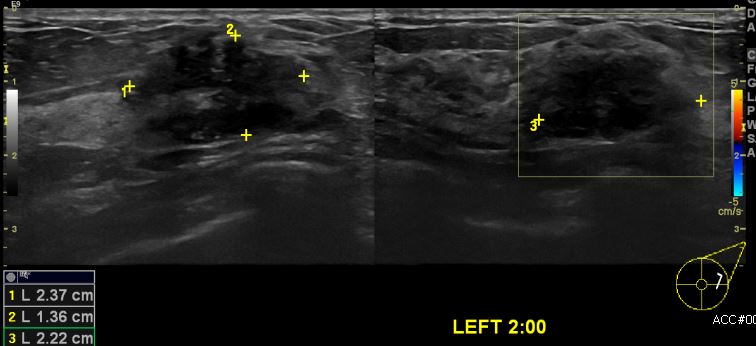

건강검진상 이상소견으로 내원하신 40대 여성분으로 좌측 2시 방향에 의심스러운

멍울 조직검사 시행하여 좌측 침윤성 유관암 진단 되었습니다.